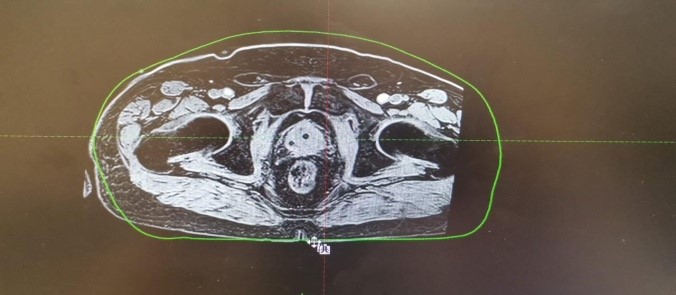

МРТ-топометрия